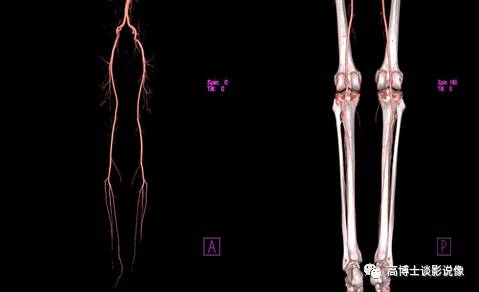

九、双下肢血管VRT重建

下肢血管VR重建可整体、直观的显示下肢血管的解剖结构及有无变异情况。